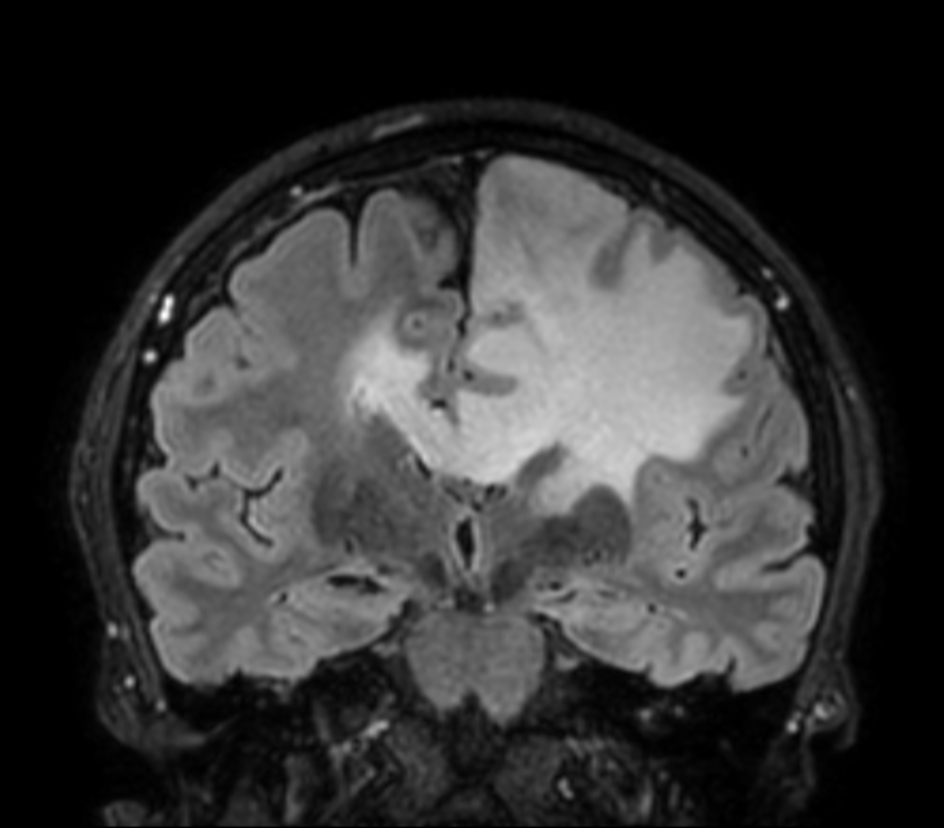

3D VIEW - T2w FLAIR (coronal reformat)